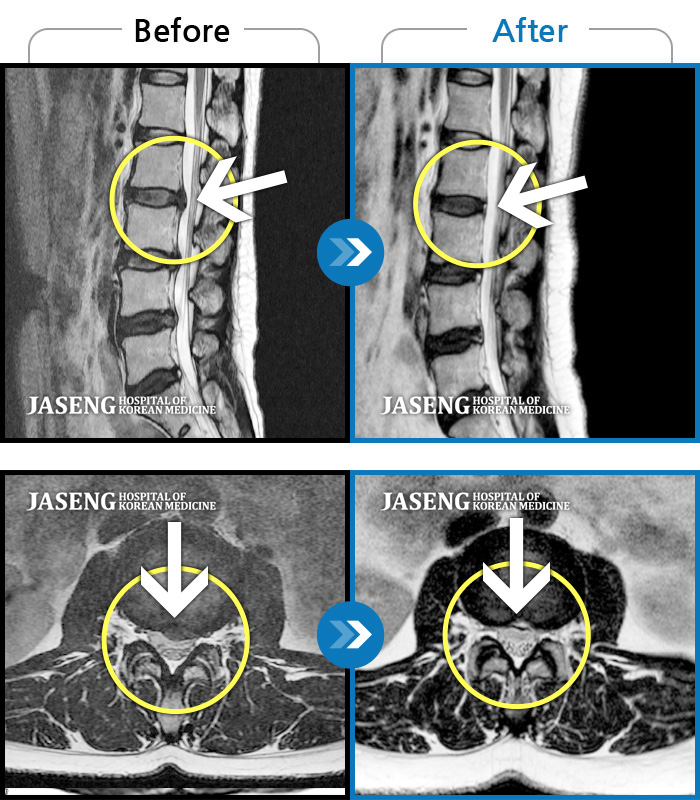

허리디스크

강남 · 강만호 원장

허리 통증 및 왼쪽 다리 근력저하 감각저하로 일상생활이 불가능했습니다.

촬영시기

2024.05.18 ~ 2025.12.03

2025.12.19

조회수 101